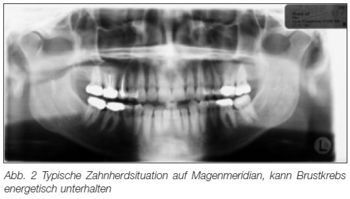

Bild aus einem Artikel von Thomas Rau bei "Sanum-Post"[2]